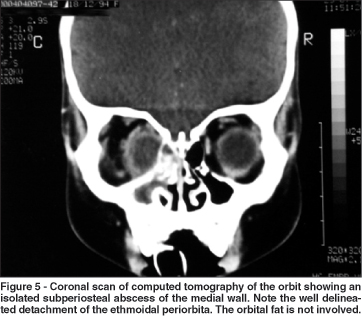

In order to categorize the radiological patterns of cellulitis the following guidelines were adopted. Diffuse fat infiltration was characterized by an increased density of the extra- or intraconal fat. The limits of the transition between the normal fat and the enhanced fat density were typically gradual and not well defined. A subperiosteal abscess was diagnosed when the periorbita was elevated from at least one orbital wall adjacent to a paranasal sinus. Finally, an orbital abscess was defined whenever an abnormal heterogeneous density was found (with or without ring appearance) within the orbital fat.

In all cases intraorbital changes could be detected. Diffuse infiltration was seen as an isolated feature in 11 patients (24.44%) who were successfully managed using medical treatment with intravenous antibiotics alone (Figure 4). As shown in Figure 5, subperiosteal abscesses were diagnosed in 28 patients (62.23%). The detached periosteum was usually well demarcated, defining the border of fluid collection. In 9 patients (20%) there was a diffuse fat infiltration at the boundaries of periorbita elevation (Figure 6). Orbital abscesses were seen in 6 patients (13.33%, Figure 7). All of these cases were surgically confirmed.

Subperiosteal abscesses can also lead to intracranial complications and to visual impairment(37-38). However, this condition has distinct characteristics. The fluid collection is limited by the periorbita with varying amounts of fat infiltration beyond the well demarcated border of the detached periorbita. It is well known that in some cases of periorbita detachment there is no pus between the bone wall and the periorbita, the periosteum elevation being caused by hemorrhagic or clear fluid and edema(39).